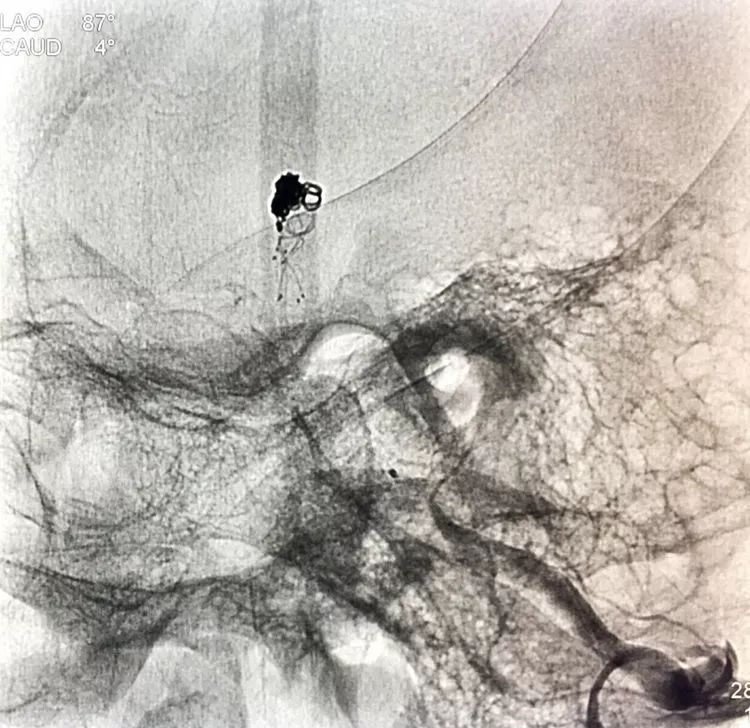

旋转增强器透视观察各个投照角度弹簧圈的分布情况,侧位透视发现瘤腔后部的弹簧圈分布疏松,形成死腔,看来革命还未成功,同志尚需努力呀!

回头再观察左椎动脉造影的三维成像,发现瘤腔确实有向后方突出的分叶,明确弹簧圈团后部的空虚处仍是瘤腔的一部分

此刻微导管的管头被支架压在瘤腔前部,显然无法再深入到瘤腔后部的死腔,这根直头的微导管该结束使命了,